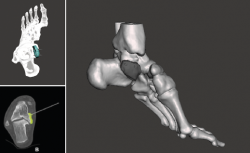

Se trata de un paciente varón de 35 años que, tras una precipitación, presenta impotencia funcional en el miembro inferior. Tras la valoración clínica y radiológica, se observa un estallido de la parte posterior de la cúpula astragalina (Figura 1).

Utilidad de la impresión 3D: debido a la complejidad de la lesión, se decide tratarla con un aloinjerto estructural. Se decidió imprimir un modelo 3D del defecto óseo para poder tallar el injerto con la forma más parecida al defecto original.

- Obtención de la forma real del defecto combinando el astrágalo con una imagen especular del astrágalo contralateral (Figura 2).

- Impresión 3D del defecto del astrágalo y guía para la colocación de las agujas (Figura 3).